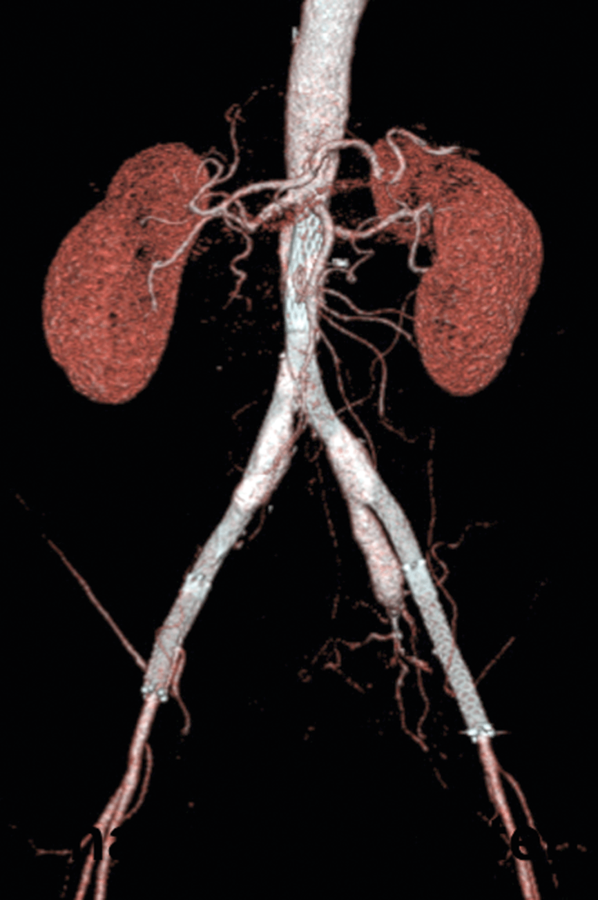

Abb. 1: Aortoiliakale Okklusion durch eine besondere Variante der PAVK, das Leriche-Syndrom. Mit der endovaskulären Behandlung gelang die Wiedereröffnung der Gefäße (danach). Abb. 1: Aortoiliakale Okklusion durch eine besondere Variante der PAVK, das Leriche-Syndrom. Mit der endovaskulären Behandlung gelang die Wiedereröffnung der Gefäße (danach). © Krankenberg H. Hamburger Ärzteblatt 2020; 74: 13-16 © Hamburger Ärzteverlag, Hamburg